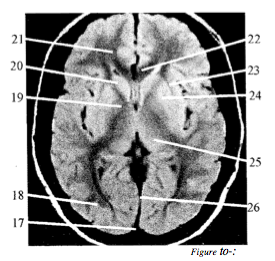

Question 2

Question

Label with just the letter: Q. Internal capsule, R. Lentiform nucleus, S. Superior sagittal sinus, T. Head of caudate nucleus, U. Thalamus, V. External capsule, W. Corpus callosum, X. Frontal lobe, Y. Occipital lobe, Z. Interhemispheric fissure

Answer

• T

• X

• Q

• Y

• S

• W

• V

• R

• U

• Z